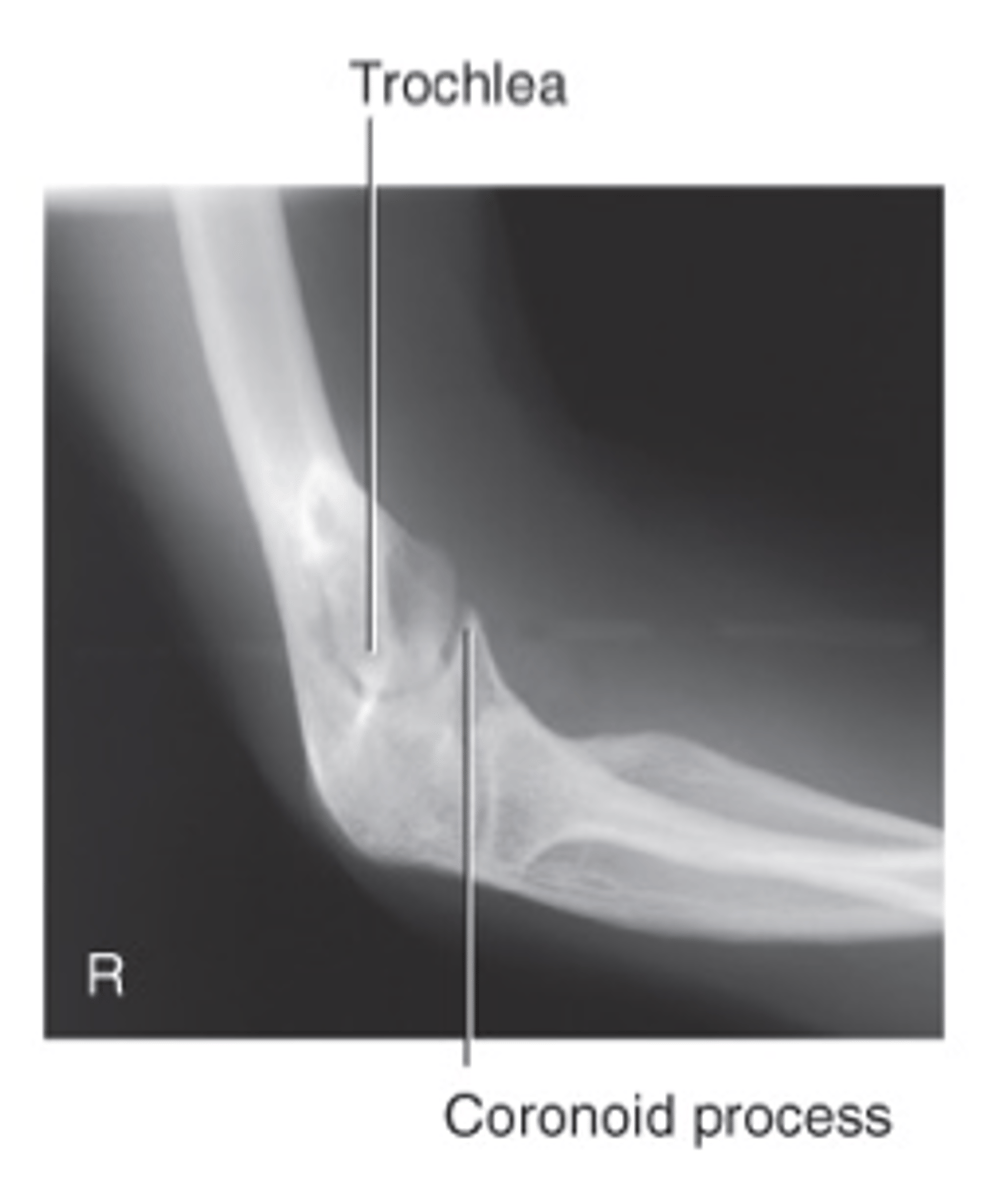

Axial lateromedial for coronoid process elbow